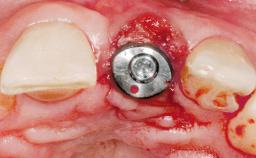

Type of Implants One-Piece

Attachment One-Piece

Bone Augmentation Horizontal|Simultaneous

Augmentation Materials Xenogenous|Membrane

Placement Protocol Immediate implant placement

Tooth Site Maxillary incisor or canine